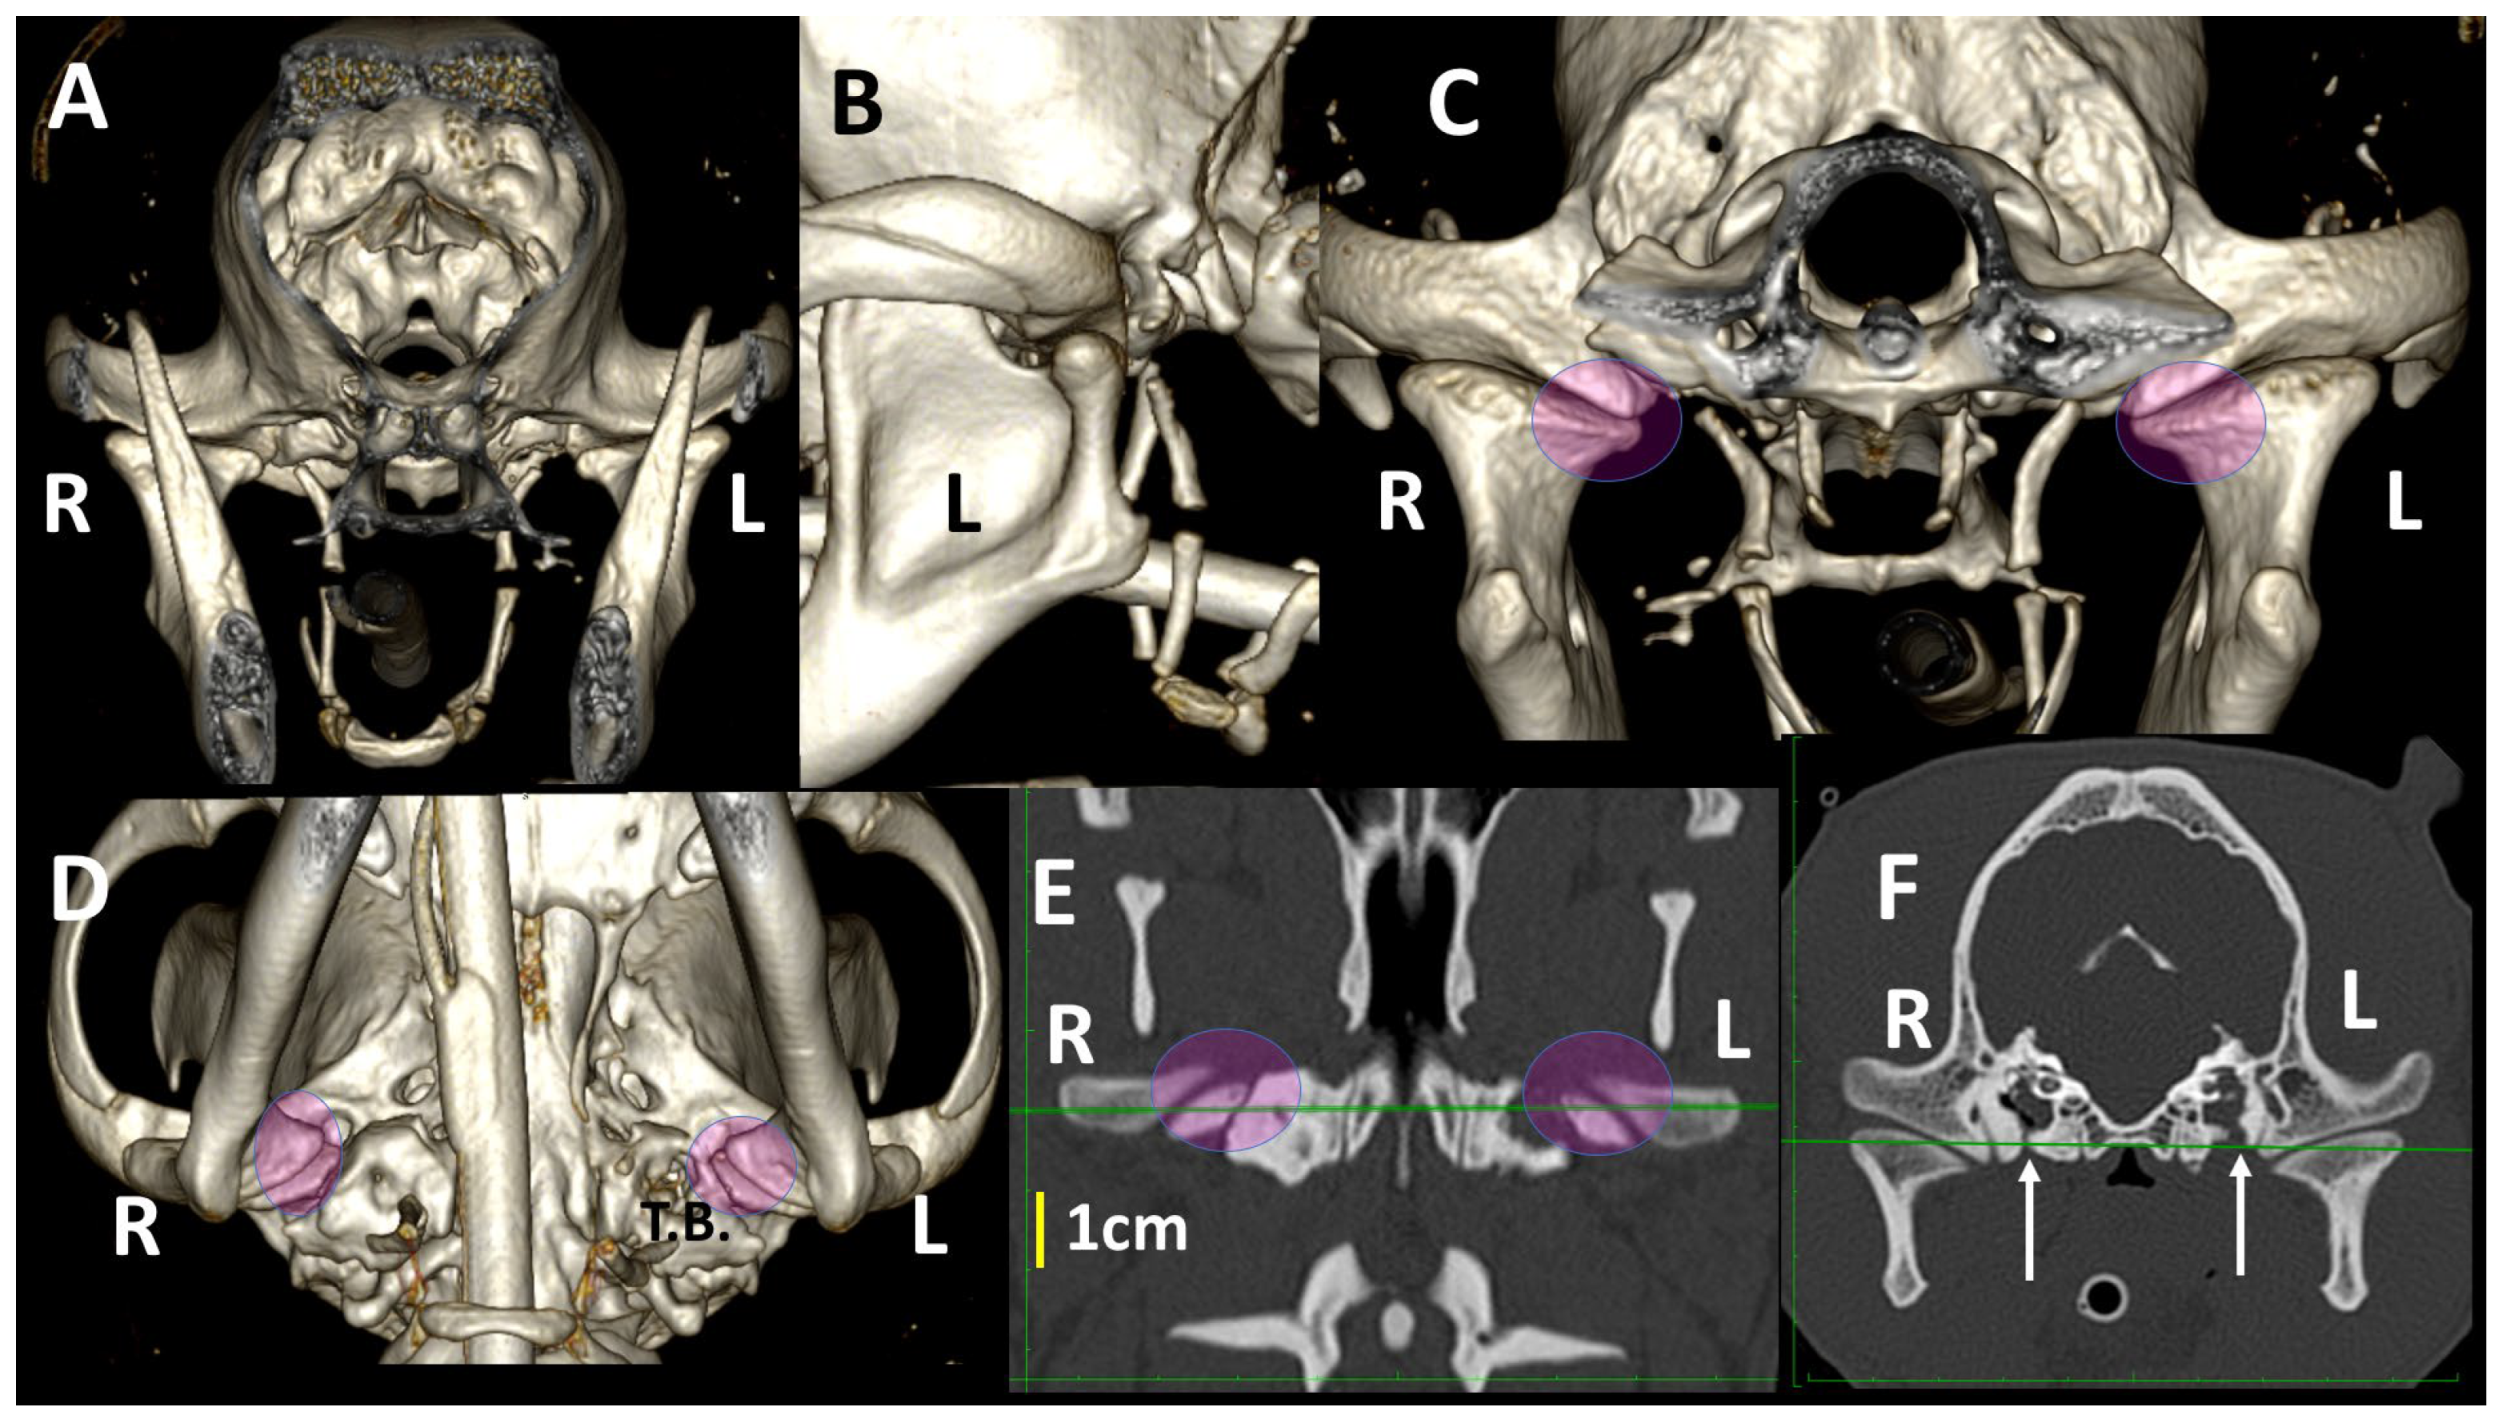

3.4. A Pictorial Essay of 3DVR Images in Some Pathological Cases